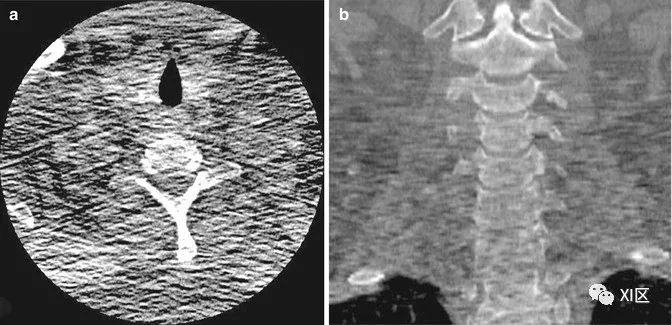

量子斑点。(a) 颈椎的轴位和(b)冠状位CT图像显示,由于大的体型和光子饥饿,解剖清晰度较差,特别是在肩部。在这些图像中,由于低信噪比,量子噪声更加明显。